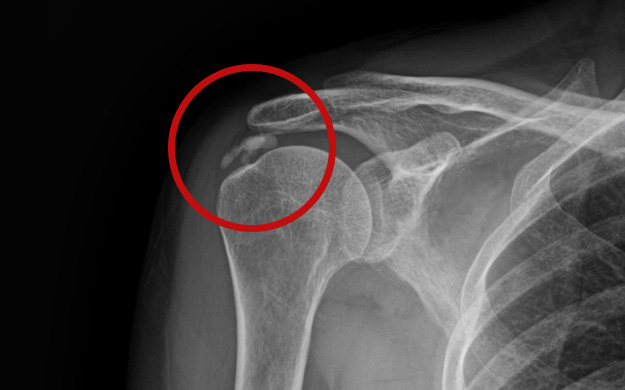

어깨 힘줄 내부에 칼슘 석회가 침착되어 힘줄의 손상과 함께 통증을 유발하는 질환입니다.

어깨 속에 석회가루가 쌓여 통증을 유발하는 석회화건염은

움직임이 제한되고 혈액순환 장애와 염증반응을 유발합니다.

석회는 신체 어느 부위에서나 발생할 수 있으나 어깨에 가장 많이 발생합니다.